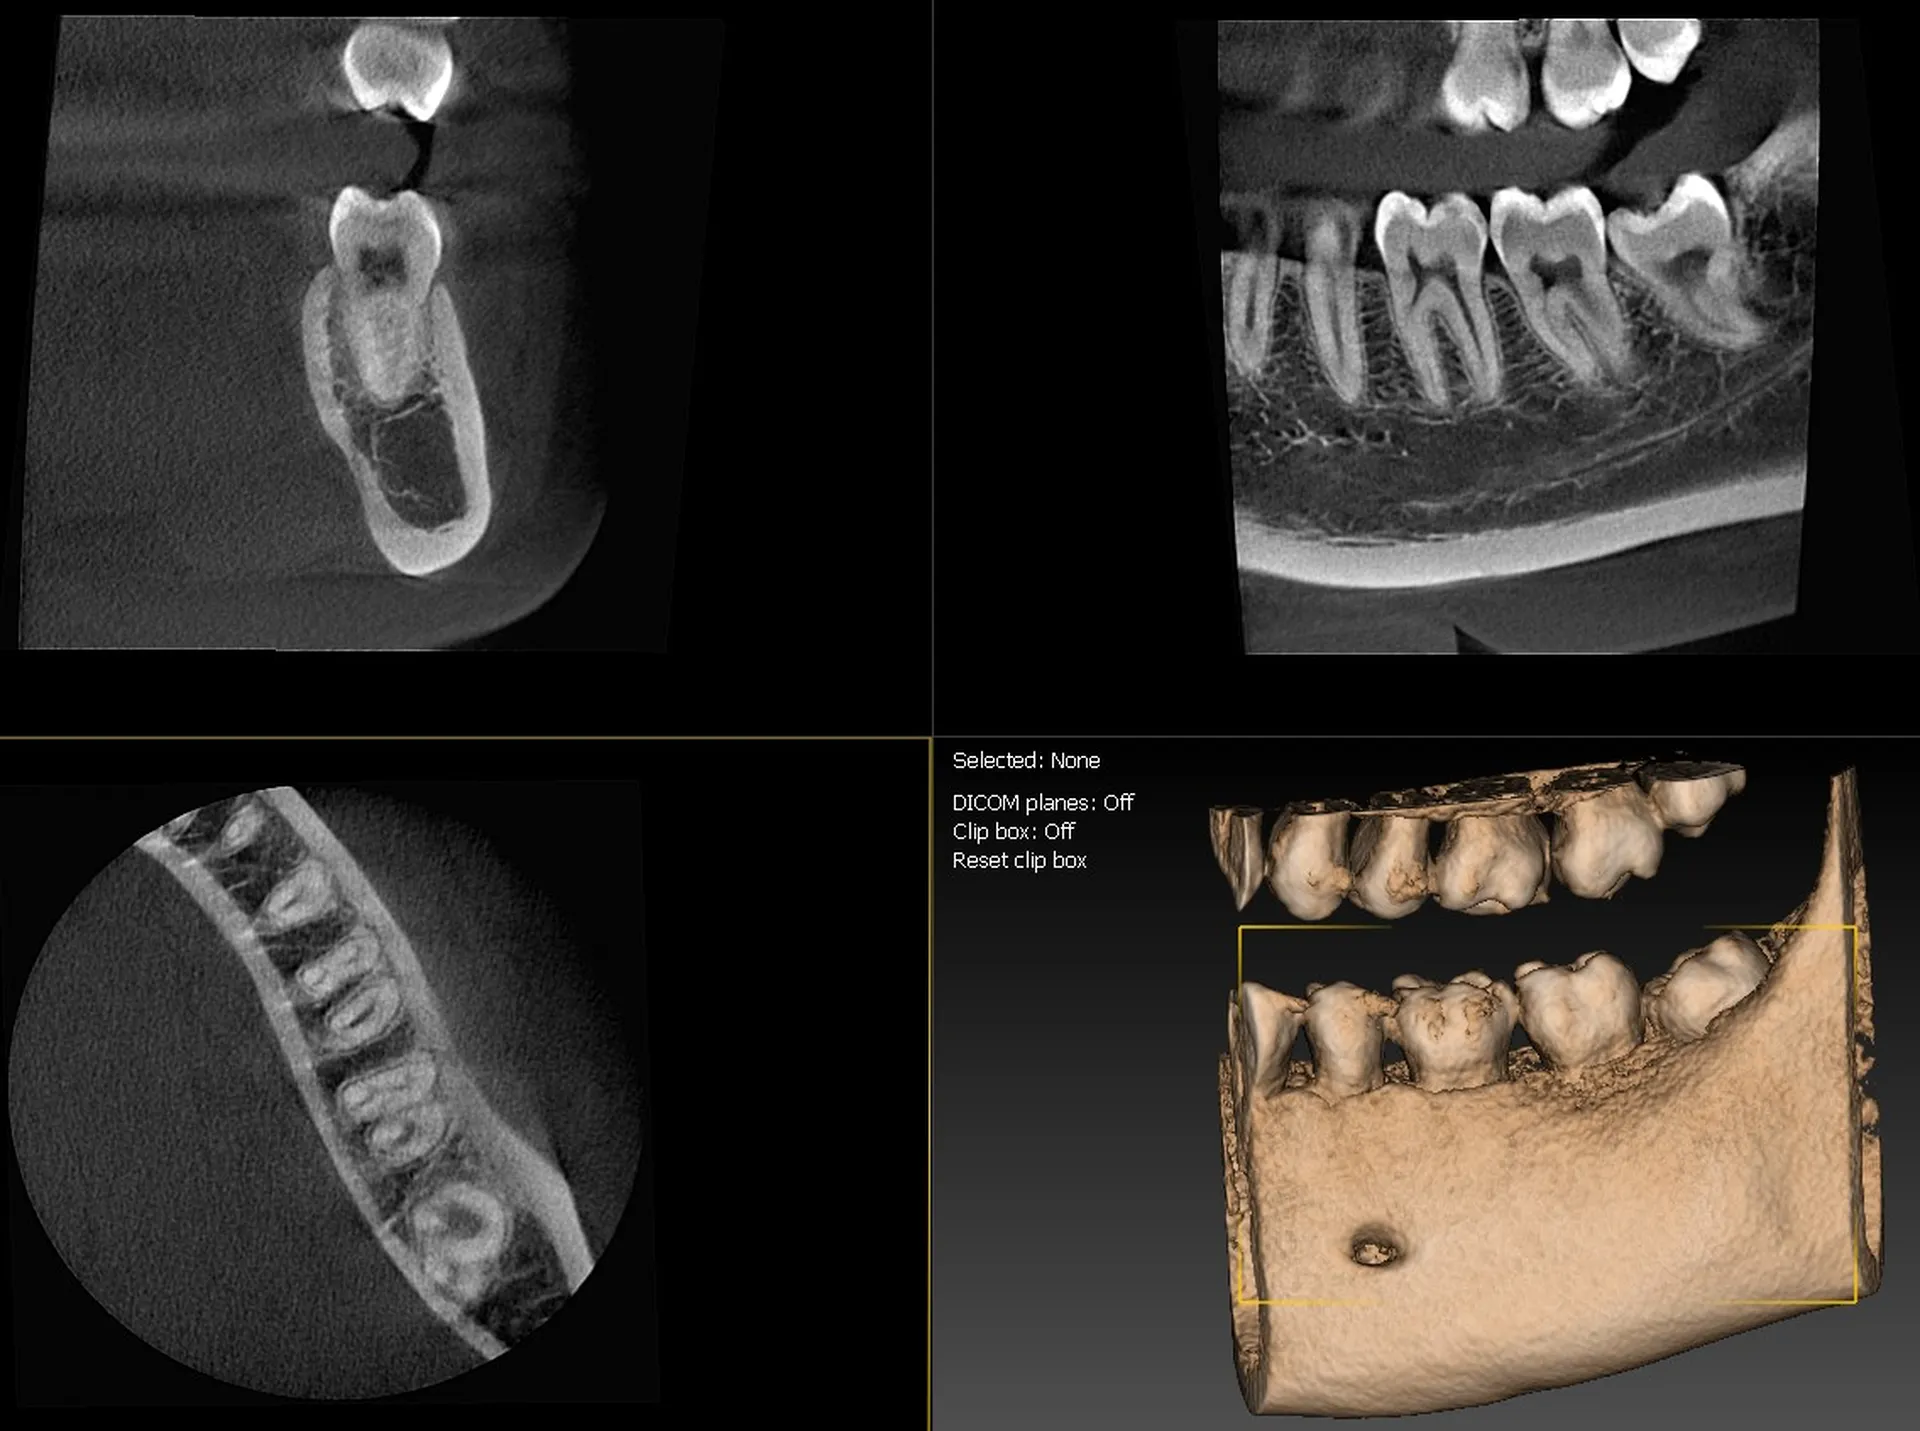

L’I-Max 3D XPRO est un système Cone Beam multifonction 4-en-1 conçu pour fournir une imagerie dentaire ultra-précise dans divers modes : panoramique, 3D, céphalométrie et scan d’objets (modèles en plâtre, porte-empreintes).

La qualité d’image est exceptionnelle, avec une résolution de 70 microns, assurant une finesse diagnostique accrue.

Le champ d’imagerie (FOV) peut être ajusté entre 16×11 cm à 5×5 cm, ce qui permet de cibler précisément la zone d’intérêt et de limiter l’exposition aux rayonnements.

La technologie Super IGZO est au cœur de ce système, avec des innovations telles que le traitement IA (algorithmes de débruitage), le Focus Scintillator pour réduire le bruit et l’algorithme AutoMAR pour atténuer les artéfacts métalliques.  Le positionnement "face à face" améliore le confort du patient et la reproductibilité des prises de vue.

Grâce à sa compacité (empreinte au sol inférieure à 1 m²) et son installation murale ou en colonne, l’appareil peut s’adapter aux contraintes d’espace des cabinets.  L’interface est intuitive, facilitant le passage entre les modes 2D et 3D, et la planification implantaire est supportée par le logiciel QuickVision 3D intégré pour visualiser, simuler et guider les interventions.